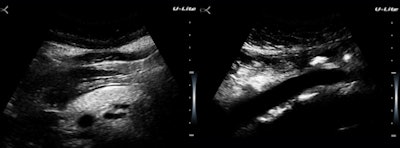

One of the first cases I was asked to see was a 23-year-old man with painless swelling of the right half of the scrotum for the previous five years. The patient wanted to know if this might affect fertility (figure 2).

Figure 2: The right testis is embedded within a thick attenuating rind.Our impression was fibrous pseudotumor of the tunica vaginalis, which is a reasonably rare occurrence. There were no additional findings supportive of filariasis or schistosomiasis, which are even rarer with unilateral scrotal presentations. This case illustrates the challenge for the examiner to be familiar with the area he or she is imaging, or to know how to go from image findings to the proper reference source immediately.

This is a strength of radiology and one that we share uniquely with pathology. This particular example was easy, because the diagnosis is just a descriptive term, but we're not always as lucky. The clinic population has a high prevalence of cholelithiasis, obesity, hypertension, and metabolic syndrome (figure 3).

Figure 3: An obese woman with a fatty pancreas and a pristine aortic wall.There are two reasons why I am using up limited image real estate here with something as pedestrian seeming as a fatty pancreas. The diagnostic issue is not identifying obesity but in assessing cardiac and insulin resistance risks. Like fatty liver, pancreatic fat is a visceral fat deposition a big step closer to metabolic syndrome. The second is that the U-Lite does a much better job in the presence of obesity than I would have anticipated. Maybe this has to do with the submillimeter range gating?